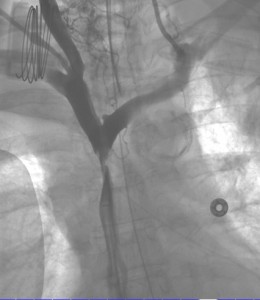

The diagnosis is usually clinical. Once clinical suspicion arises, imaging needs to be utilized. Sometimes we begin to suspect this diagnosis because of a combination of typical clinical signs and symptoms and a widened mediastinum on plain chest radiograph. However, the best imaging study for diagnosing an obstruction in the superior vena cava or compressing mass is CT with intravenous contrast. MR and PET-CT may have their value in specific cases, though. Other than the diagnosis of superior vena cava compression or thrombosis, the cause needs to be identified fully. Therefore, many times biopsy and pathological tests are needed to compliment imaging. Tissue may be obtained in various methods including from sputum, pleural fluid, mediastinoscopy or open surgical biopsy. Before intervention (see ‘treatment of superior vena cava syndrome’), venography may be needed, although it is sometimes a combined diagnostic and therapeutic intervention.

We use superior vena cava stenting in patients with SVCS secondary to malignancy as a rescue procedure in patients with severe swelling or shortness of breath. Stents may be used either as secondary, rescue, treatment when chemotherapy and or radiation have failed or as first line treatment. After successful stenting, symptoms are expected to resolve within 24-48 hours.

The durability of palliative superior vena cava stenting procedures is rather good considering the usual patient overall condition. Therefore, the superior vena cava syndrome does not usually return to bother the patient and proper treatment endeavors can be sought. However, recurrence happens in in 10-20% of patients, and then re-treatment is needed in a similar manner to the first one. Superior vena cava stents may be self-expanding or balloon expandable. There are several types of stents that are in use for treatment of superior vena cava syndrome. These include self-expanding stents and balloon-expandable stents. Choice of the proper stent depends on how tight the superior vena cava stenosis is, the length of the lesion and on vessel curvature.